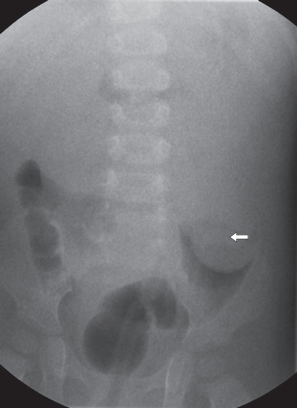

Fig. 56.2

Ultrasonido del mismo paciente que demuestra una anomalía en el sitio señalado en la Fig. 56.1B. Se observa el aspecto de telescopado del intestino en el corte longitudinal (izquierda) y el signo en diana o “target sign” en el corte transversal (derecha), característico de una intususcepción.